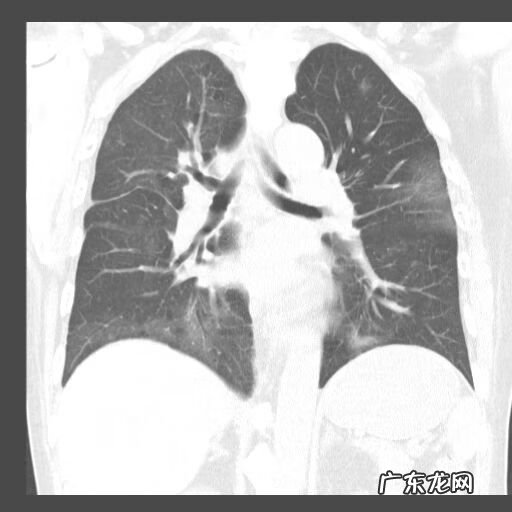

孤立性肿块型在临床非常难以鉴别,我只是把自己的经验和大家分享 。肿块型好发于外周,右肺下叶较多见;尖角征,周边伴毛刺及索条,周围伴有磨玻璃密度影;病灶内可见坏死和空洞,空洞较小,内壁光整;内有支气管气相及空腔;病灶临近胸膜时,与胸膜呈宽基底相连,胸膜可增厚粘连,胸膜下脂肪层存在 。